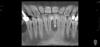

art.podzhigant Опубликовано 7 июня, 2013 Поделиться Опубликовано 7 июня, 2013 женщина,50 лет, 31 зуб сама вынимала из лунки и вставляла обратно несколько месяцев. Была сдержанна при разговоре,чтоб случайно не скаканул изо рта Не ходила к гигиенисту ,потому как уверена,что ее зубной камень держит зубы...(наверное она права) Теперь стоит вопрос с тактикой лечения в этой области. Гигиену слава богу уже сделали, зуб 3.1 фиксирован адгезивно к соседним. Фотографий внутриротовых пока нет. Я бы предложил ей убрать все 4 резца и имплантировать 4.2 и 3.2 ,в обл 3.1 - поработать с костью и мягкими тканями,чтоб создать условия для понтика... Пациентка хотела бы ограничиться костной пластикой в обл. 3.1 и постановкой одного импланта.ВАШИ ВАРИАНТЫ? Ссылка на комментарий

art.podzhigant Опубликовано 7 июня, 2013 Автор Поделиться Опубликовано 7 июня, 2013 (изменено) На 3д моделировании виднеется верх фронт... Гипердиагностирует? У нее перегрузки и блока нет? Предверие и биотоп глубокое и толстый?Я бы сделал пластику кост/слиз , кюретаж в области 41 32 . адгезивный 3.1 с шинированием с клыка по клый на 2 месяца... Будет плюс ткань и увидим повадки гигиены Ж50... А потом только 31 импл..есть в этом здравый смысл. но кюретажить там нечего...повторюсь,к сожалению фотографии нет,но представьте полностью эпителизированную лунку с трехстворчатым дефектом кости.То есть под слизистой здоровой,здоровая кость. зуб 3.1 находился в ложе и со всех сторон кроме вестибулярной граничит со слизистой.(С ВЕСТИБУЛЯРНОЙ ВООБЩЕ НИЧЕГО НЕТ)Убрав его получаем дефект по форме корня . Вертикально довольно много кости надо добавлять...Перегрузки есть,функциональные группы конечно же. блока нет. биотип тонкий. Камня было ооочень много. Изменено 7 июня, 2013 пользователем art.podzhigant Ссылка на комментарий

art.podzhigant Опубликовано 7 июня, 2013 Автор Поделиться Опубликовано 7 июня, 2013 а если вообще имплантацию откинуть, постоянный мост адгезивный там прокатит?Прокатит конечно. Только что делать с сантиметровым промывным пространством.? Если его закрывать за счет кантилевра ,то нет эстетики,если за счет костной пластики и мягких тканей,то возможно...в этом случае почему бы не поставить имплантат? Немного устаревший критерий выбора конструкции относительно прогноза выживаемости этой конструкции карлом мИшем был продиктован когда-то.И именно поэтому мне кажется,что более успешной будет конструкция с опорой на импланты в позициях 32 и 42,чем адгезивный 3.1...Лезть в область 3.1 для создания объема костной ткани все равно придется. А вот удалять или нет остальные три зуба я пока для себя не аргументировал.и ту и другую технику выполнить не так сложно... вот и хочу от коллег более конкретного ответа на поставленный вопрос..удалять все зубы и ставить 2 импланта с нкр в обл. 3.1? прошу аргументироватьили не удалять 32,42,41,а делать нкр 3.1 с титановой сеткой + имплант попозжеили нкр + адгезивный шинирующий мостик? насколько нкр с сохраненными зубами(не инфицированными) в данных условиях оправдано? Ссылка на комментарий

DShu Опубликовано 7 июня, 2013 Поделиться Опубликовано 7 июня, 2013 Прокатит конечно. Только что делать с сантиметровым промывным пространством.? Если его закрывать за счет кантилевра ,то нет эстетики,если за счет костной пластики и мягких тканей,то возможно...в этом случае почему бы не поставить имплантат? Немного устаревший критерий выбора конструкции относительно прогноза выживаемости этой конструкции карлом мИшем был продиктован когда-то.И именно поэтому мне кажется,что более успешной будет конструкция с опорой на импланты в позициях 32 и 42,чем адгезивный 3.1...Лезть в область 3.1 для создания объема костной ткани все равно придется. А вот удалять или нет остальные три зуба я пока для себя не аргументировал.и ту и другую технику выполнить не так сложно... вот и хочу от коллег более конкретного ответа на поставленный вопрос..удалять все зубы и ставить 2 импланта с нкр в обл. 3.1? прошу аргументироватьили не удалять 32,42,41,а делать нкр 3.1 с титановой сеткой + имплант попозжеили нкр + адгезивный шинирующий мостик? насколько нкр с сохраненными зубами(не инфицированными) в данных условиях оправдано?Без удаления соседей НКР не прокатит. Как я уже написал, дефект должен быть ограничен костными пиками. Скажи, почему ты так настойчиво приговариваешь 42 к удалению?) по мне он ничего себе Ссылка на комментарий

johniola Опубликовано 8 июня, 2013 Поделиться Опубликовано 8 июня, 2013 Без удаления соседей НКР не прокатит. Как я уже написал, дефект должен быть ограничен костными пиками. Скажи, почему ты так настойчиво приговариваешь 42 к удалению?) по мне он ничего себепочему не прокатит? дефект как я понял только с вестибулярки.при удалении 3 зубов вы рискуете получить ещё больший дефект.я бы попробовал сохранить,или по крайней мере решение принял бы на месте после раскрытия. Ссылка на комментарий